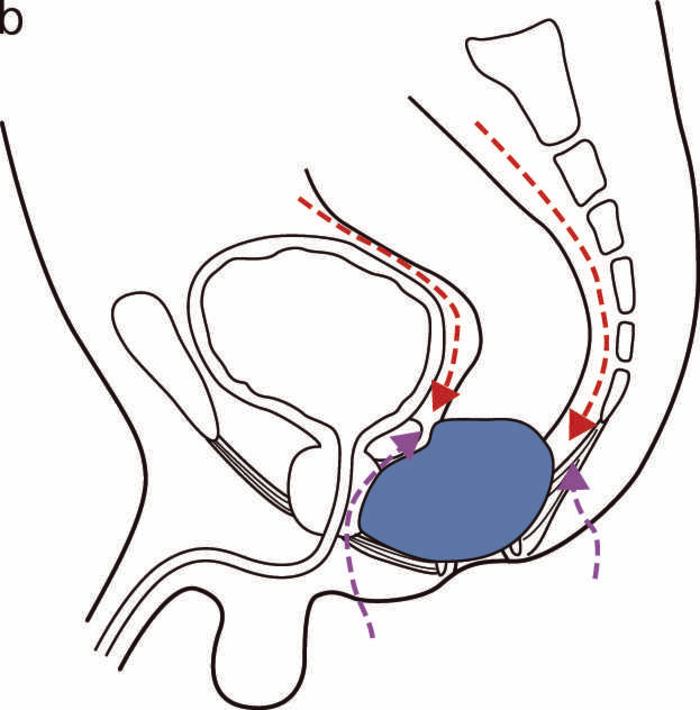

(1)体位,生検部位(図23)

全身麻酔下に,砕石位もしくはJack-knife位で行う。生検を行う部位は,歯状線付近を全周性に3カ所程度行う。

(2)手 順(図24)

視診,触診,直腸診で診察を行う(図24a)。診察でターゲットとなる部を認めた場合は,その部位から生検し,ない場合は肛門鏡で視野を確保し,歯状線近傍から全周性に3カ所ほど行う(図24b)。痔瘻を伴う場合は,非活動性,瘢痕化している場合でも,瘻管内から生検を行う(図24c)。

(3)狭窄病変がある場合(図25)

小指,示指で愛護的に拡張した後(図25a),ブジーを使って,内視鏡検査が可能な程度まで拡張を行う(図25b)。内視鏡により直腸の観察,生検を併せて行う(図25c,d)。

図23 肛門管粘膜,瘻管内からの生検